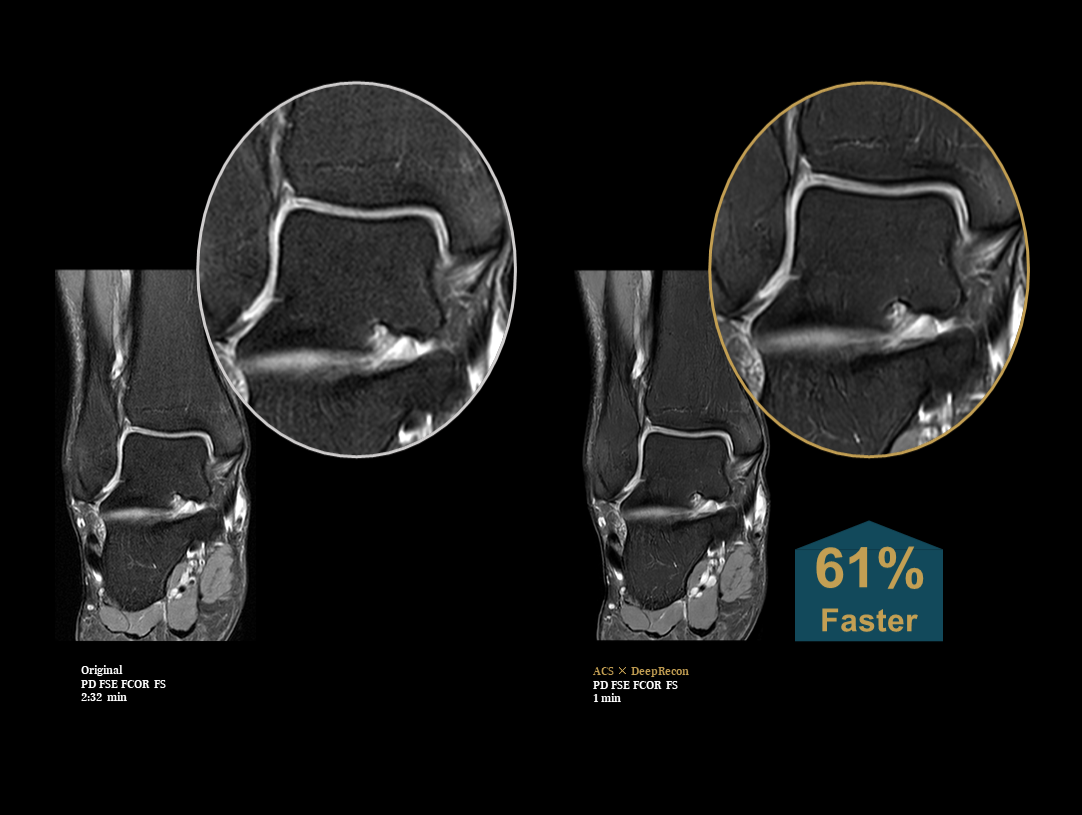

The high performance gradients improve data acquisition and scanning speed, which achieves higher work efficiency.